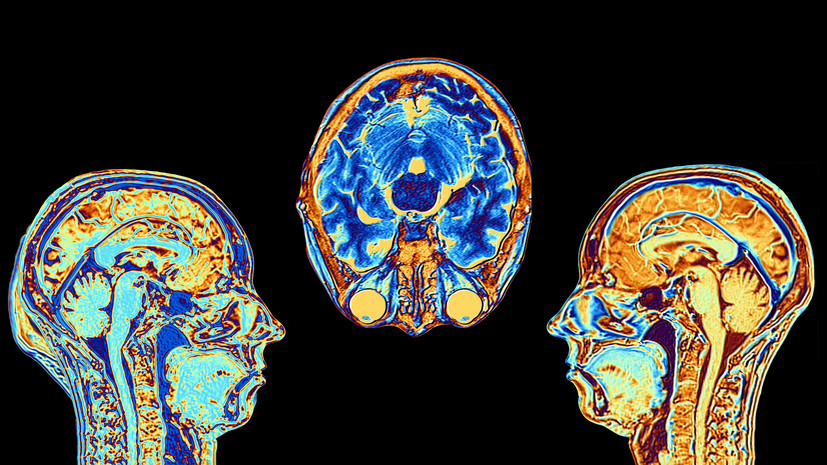

MRI scans are key in medicine. They give detailed images of organs and tissues. This helps doctors make accurate diagnoses and choose the right treatments for many health issues. Why would a doctor order an MRI of the brain? Discover key reasons and benefits of brain MRI scans. lets check out

MRI scans of the brain are key for diagnosing many neurological issues. They give detailed images that doctors use to spot problems and plan treatments.

Doctors use MRI scans to find conditions like multiple sclerosis, Alzheimer’s, and Parkinson’s. These scans show small changes in brain tissue. This is vital for catching problems early and treating them quickly.

MRI scans are very helpful for spotting issues with the brain’s structure, like hydrocephalus or cerebral edema. Doctors can see how severe these problems are and plan the best treatment.

Detecting Brain Tumors and Abnormal Growths

MRI scans are great at finding brain tumors and growths. They can tell different types of tissue apart. This helps doctors know what kind of tumor it is and how to treat it.

Can MRI detect inflammation? Yes, MRI scans can spot inflammation in the brain. This is important for diagnosing conditions like encephalitis or abscesses. Doctors can then treat these conditions properly.